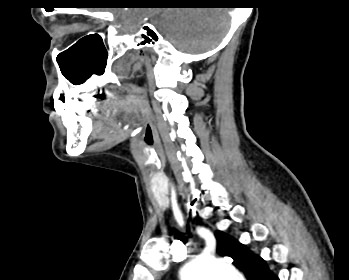

Мультиспиральная компьютерная томография – это высокоинформативный лучевой метод диагностики различной патологии мягких тканей шеи, включая воспалительные заболевания, травматические повреждения и опухолевые процессы. КТ позволяет оценить состояние щитовидной железы, паращитовидных желез, гортани, верхней части пищевода, магистральных сосудов шеи, шейных лимфоузлов и окружающих мягких тканей.

Метод КТ основан на применении рентгеновского излучения. Однако в отличие от обычного рентгена, при котором снимки производятся в одной плоскости, при КТ излучатель рентгеновских лучей постоянно двигается вокруг объекта исследования, проводя сканирование в различных плоскостях, а затем трансформируя полученные данные в цифровые трехмерные изображения. Это дает возможность визуализировать органы и ткани в мельчайших подробностях, а с помощью объемных 3D-реконструкций наглядно оценить пространственное расположение органов и патологических образований.

Для контрастирования используется йодсодержащее контрастное вещество, которое в составе рентгеноконтрастного препарата вводится в вену пациенту непосредственно во время исследования. Благодаря способности контраста поглощать рентгеновские лучи на снимках КТ хорошо контрастируются кровеносные сосуды и опухолевые образования, имеющие, как правило, развитую сосудистую сеть. Методика внутривенного болюсного контрастирования помогает обнаружить воспалительные изменения, отличить доброкачественные опухоли от злокачественных, выявить поражение лимфатических узлов и степень прорастания опухоли в магистральные сосуды и окружающие ткани.

Данное обследование позволяет оценить состояние следующих анатомических структур:

• состояние магистральных сосудов шеи, кровоснабжающих головной мозг (аномалии развития, сужения, аневризмы артерий);

• строение шейных позвонков, межпозвоночных дисков, грыжи дисков;